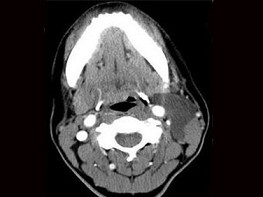

八歲患者,男性,因頸前正中包塊6年入院,查體:頸前正中舌骨下方可觸及一圓形包塊,囊性,無壓痛,隨吞咽上下活動。

8.患者腫塊圖像及影像學檢查結果見下圖,本患者應考慮為  (    )

9.如果考慮為你所選的上述疾病,手術前應該完善下面那個檢查  (    )

正確答案:8.A;9.A